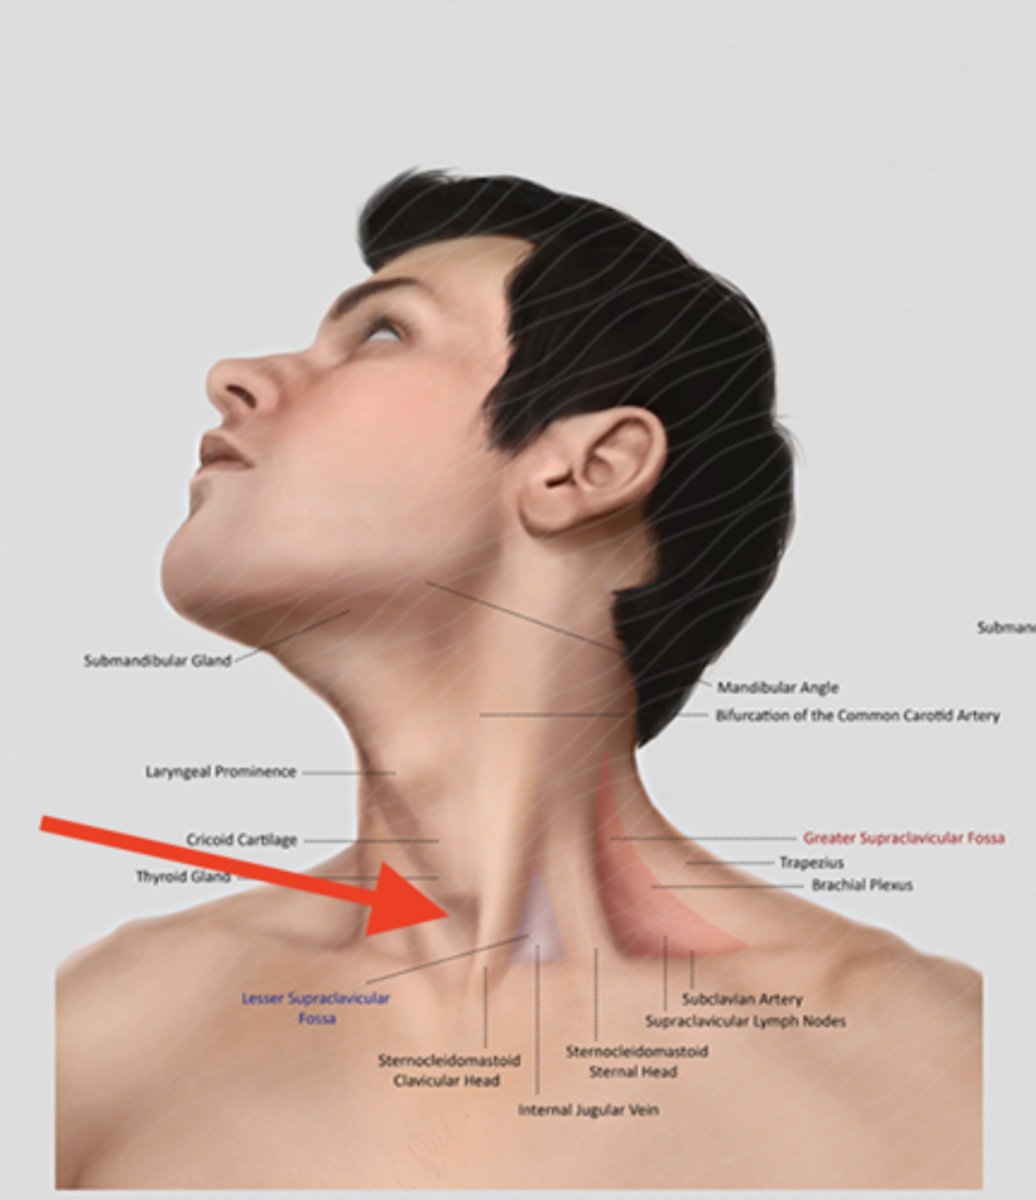

trachea (surface anatomy)

feel for trachial cartilages